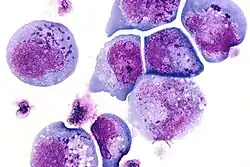

I-cells, also called inclusion cells, are abnormal fibroblasts having a large number of dark inclusions in the cytoplasm of the cell (mainly in the central area). Inclusion bodies are nuclear or cytoplasmic aggregates of stainable substances, usually proteins.[1] These metabolically inactive aggregates are not enclosed by a membrane, and are composed of fats, proteins, carbohydrates, pigments, and excretory products. When cells have an abundance of these inclusions, they are called I-Cells and are associated with neurodegenerative diseases. They are seen in Mucolipidosis II, and Mucolipidosis III, also called inclusion-cell or I-cell disease where lysosomal enzyme transport and storage is affected.